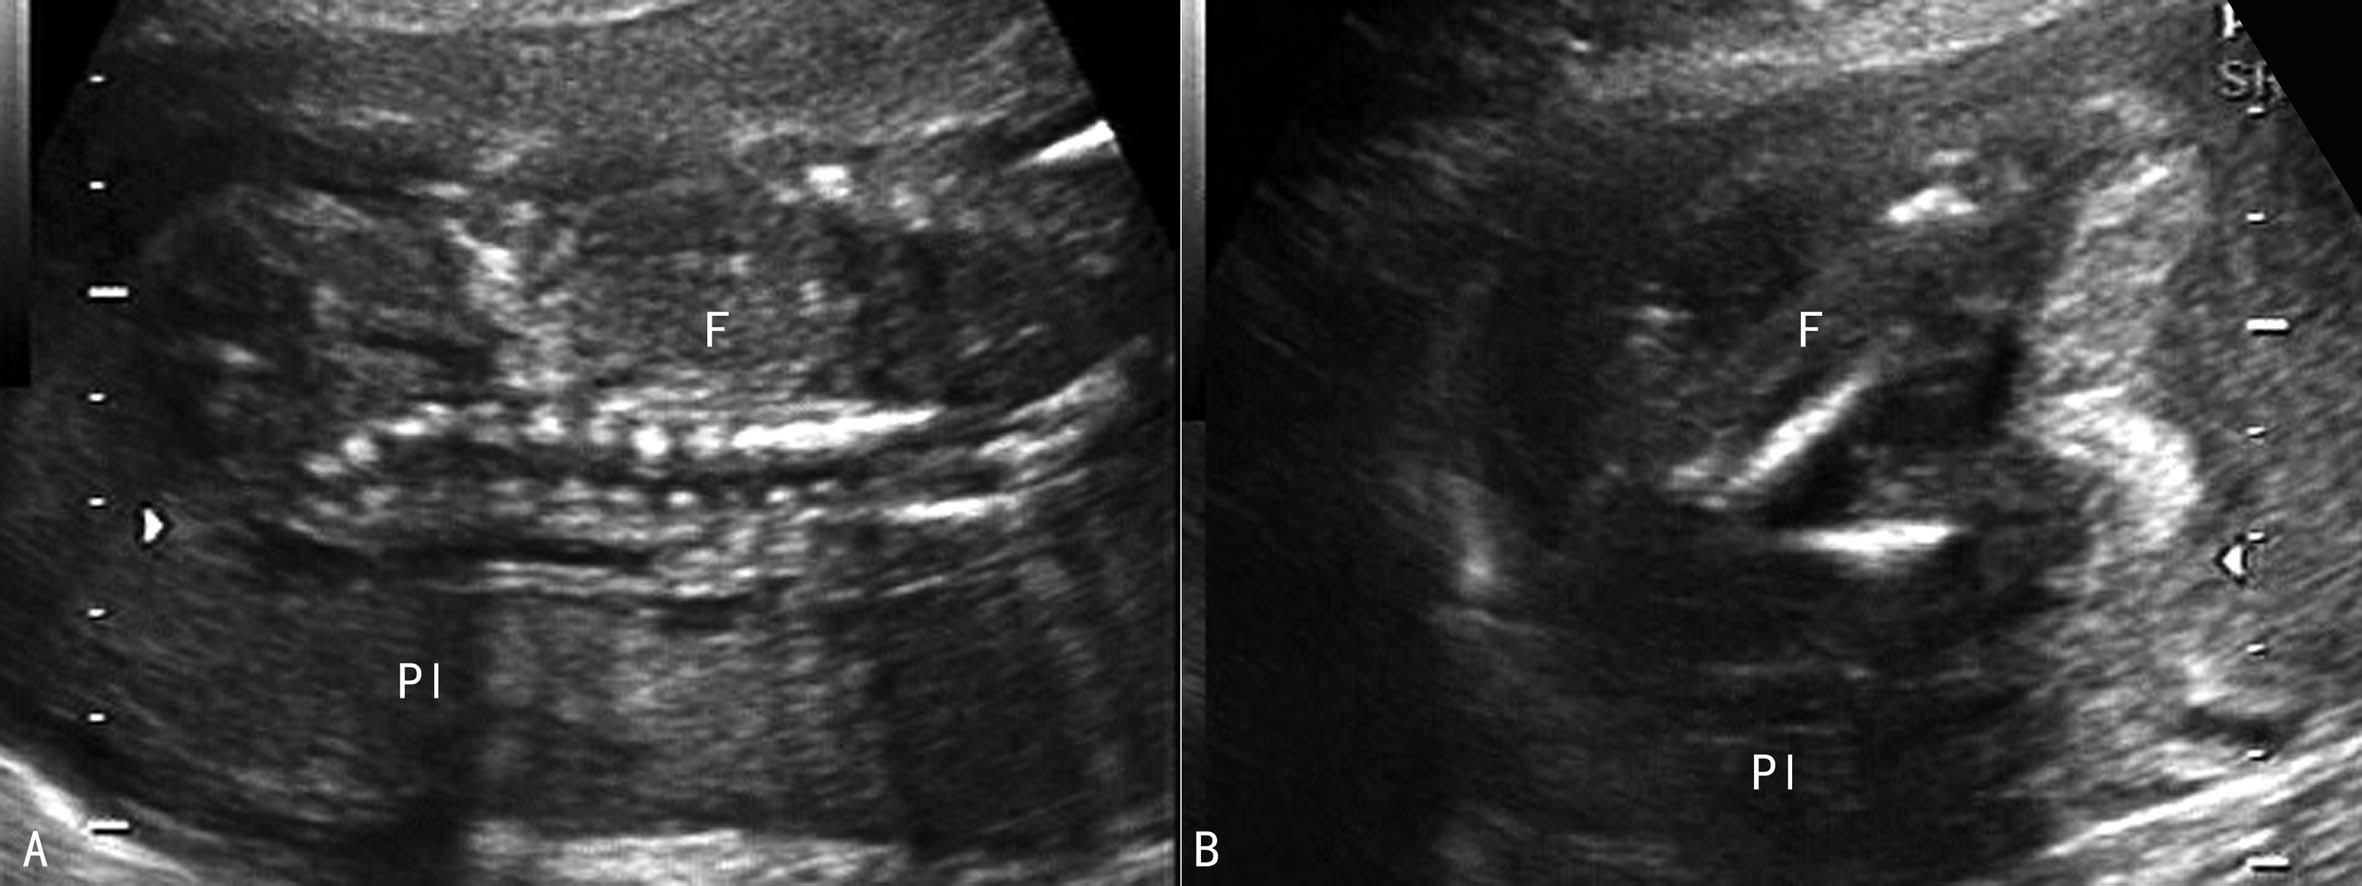

超声显像检查尚无准确的方法对羊水进行定量计算,但对于有经验的超声检查医生或明显羊水过少时通过对胎体周围羊水的观察做出羊水过少的评估并不困难(图1);超声显像检查对羊水过少的定量分析标准尚无一致的意见。以下几种不同的方法有可能对不同妊娠期的羊水过少进行评价。

2.中晚期妊娠 比较常用的是测量羊水池内径,当羊水池内径小于3cm时考虑有羊水过少(图1)。一般认为,2cm<羊水池内径<3cm时为轻度羊水过少,1cm<羊水池内径<2cm时为中度羊水过少,<1cm时为重度羊水过少;利用羊水指数评价羊水过少时,羊水指数≤5cm时可诊断为羊水过少,5.1~8cm时为低羊水量或可疑羊水过少(图2)。

图1羊水过少声像图